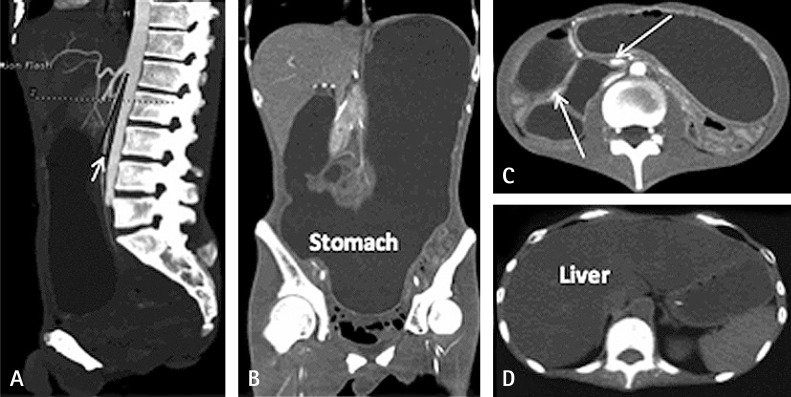

Nutrition Therapy for Mitochondrial Neurogastrointestinal Encephalopathy with Homozygous Mutation of the TYMP Gene

Jing Wang, Wei Chen, Fang Wang, Dong Wu, Jiaming Qian, Junren Kang, Hailong Li, Enling Ma

Clin Nutr Res 2015;4(2):132-136.   Published online January 16, 2015

DOI: https://doi.org/10.7762/cnr.2015.4.2.132

Mitochondrial neurogastrointestinal encephalopathy (MNGIE) is characterized by significant gastrointestinal dysmotility. Early and long-term nutritional therapy is highly recommended. We report a case of MNGIE in a patient who was undergoing long-term nutrition therapy. The patient was diagnosed with a serious symptom of fatty liver and hyperlipidemia complications, along with homozygous mutation of the thymidine phosphorylase (TYMP) gene (c.217G > A). To our knowledge, this is the first report of such a case. Herein, we describe preventive measures for the aforementioned complications and mitochondrial disease-specific nutritional therapy.